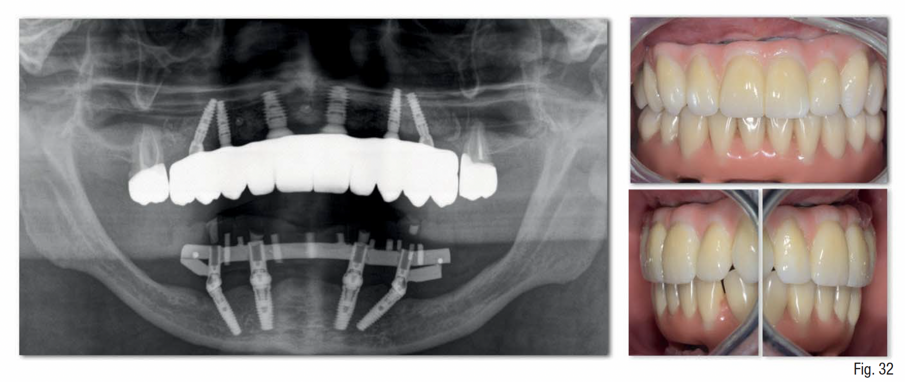

Dopo 4 mesi, è stata eseguita la riapertura degli impianti, verificando la loro osteointegrazione e applicando su di essi i rispettivi multi-unit abutment (MUA); inoltre, è stata eseguita una gestione del tessuto cheratinizzato mediante un lembo palatino a riposizionamento vestibolare (Fig. 31). Nei mesi successivi, sono state eseguite tutte le fasi protesiche che hanno portato alla realizzazione di una protesi fissa definitiva in zirconia e ceramica, avvitata sui 6 impianti, tipo “Toronto bridge” (Fig. 32). Il paziente è stato istruito alla corretta igiene domiciliare ed è stato inserito in un programma di mantenimento con sedute di igiene professionale ogni 6 mesi; e controlli radiografici mediante rx endorali e controlli clinici con smontaggio/rimontaggio della protesi fissa ogni 12 mesi (Fig. 33).